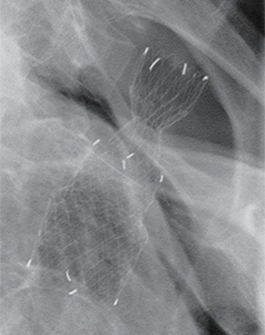

(A) The lesion was located 16cm from the incisors, 1cm below the upper esophageal sphincter (B) Post-stenting radio-graph, showing well positioned cervical stent